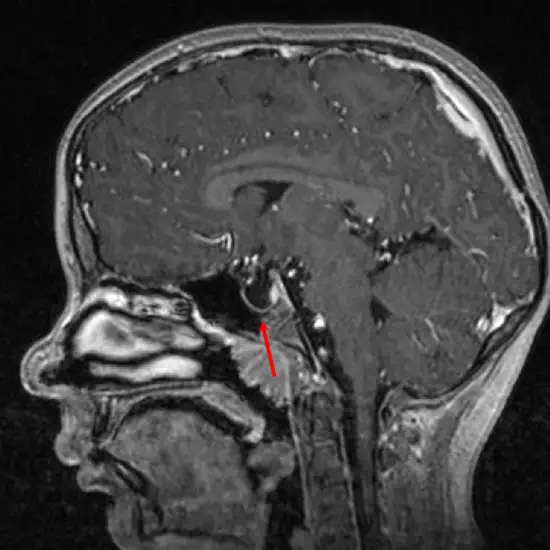

MRI Sella is Magnetic Resonance Imaging non-invasive medical diagnostic tool used to check depression in the sella brain that holds your pituitary gland and its soft tissues.

MRI Sella is a Magnetic Resonance Imaging non-invasive medical diagnostic tool for the detection of depression in the sella brain that holds your pituitary gland and its soft tissues. MRI Sella is used to show shrinkage of the pituitary gland in the sella and abnormalities like cancers, injuries, tumours etc.